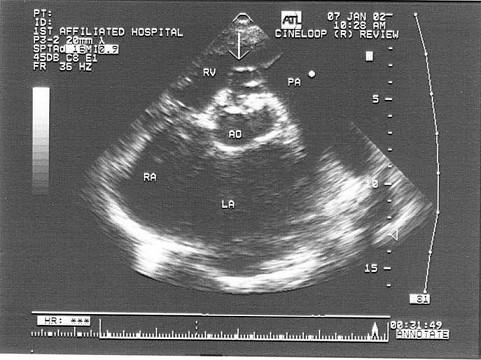

患者有明显胸痛史,其诊断可能是?(?)A.右冠窦膨隆B.嵴上型室缺C.右冠窦瘤破裂  D.右冠瓣脱垂E.左冠瓣脱垂

问题 患者有明显胸痛史,其诊断可能是?(?)

选项 A.右冠窦膨隆 B.嵴上型室缺 C.右冠窦瘤破裂   D.右冠瓣脱垂 E.左冠瓣脱垂

答案 C